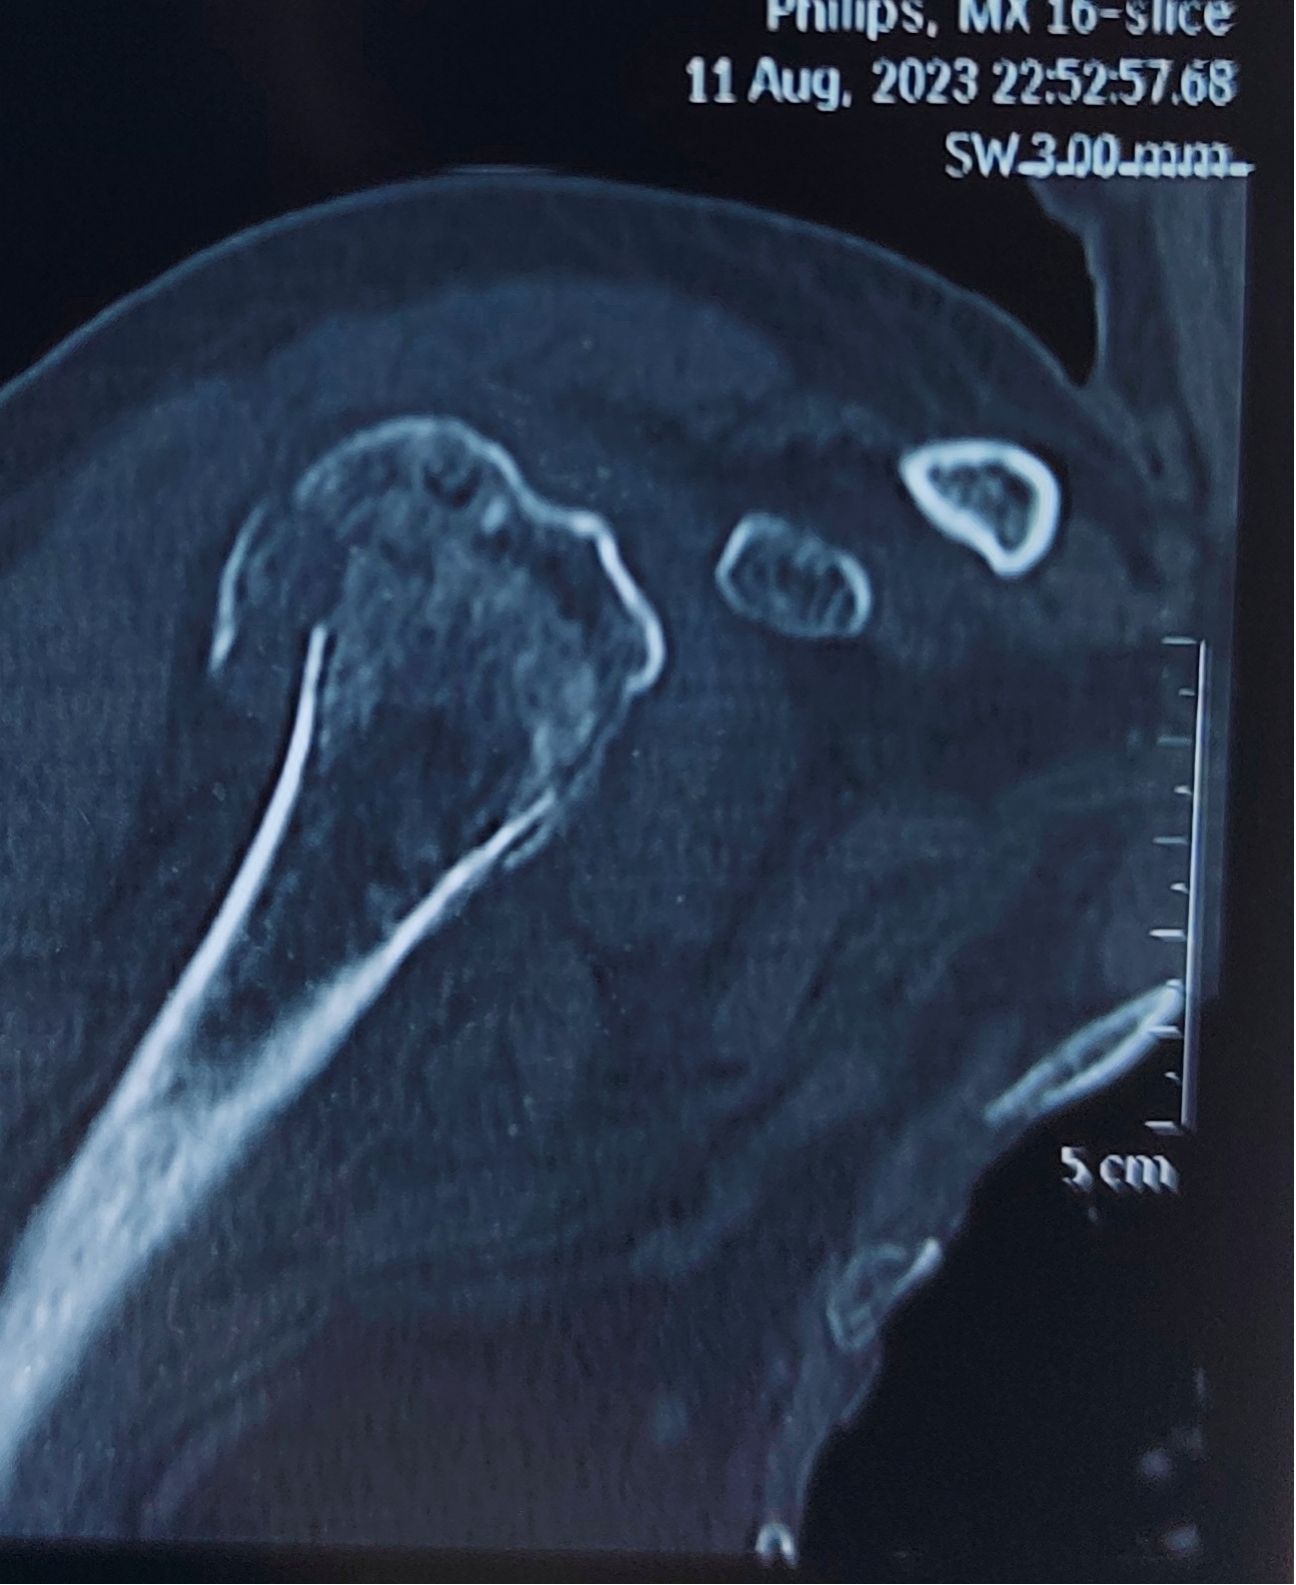

术前CT :

梁英林副主任医师仔细检查后发现,吕爷爷不仅有严重的右肱骨近端粉碎性骨折,同时还合并慢支肺气肿、高血压、肾小球肾炎、贫血等多种内科疾病,加之年纪较大,病情复杂,手术的风险也极高。于是他立即向潘建宏主任汇报相关情况,同时在医务部的组织下,与麻醉科、呼吸内科、重症医学科、肾内科、心内科等多学科专家第一时间进行了MDT会诊,根据吕爷爷的病情和身体状况仔细研讨并制定了详尽的治疗方案,将老人身体状况调整至最佳状况。